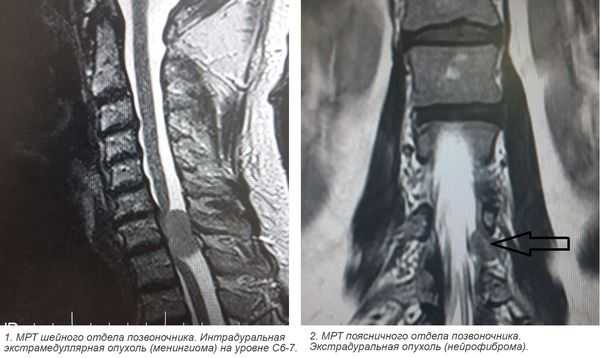

- экстрамедуллярные опухоли могут быть экстрадуральными (располагаются над твёрдой мозговой оболочкой) и интрадуральными, или субдуральными (локализуются под твёрдой мозговой оболочкой).

- менингиома (из клеток оболочек головного и спинного мозга);

- невринома (из клеток, образующих миелиновую оболочку нервов);